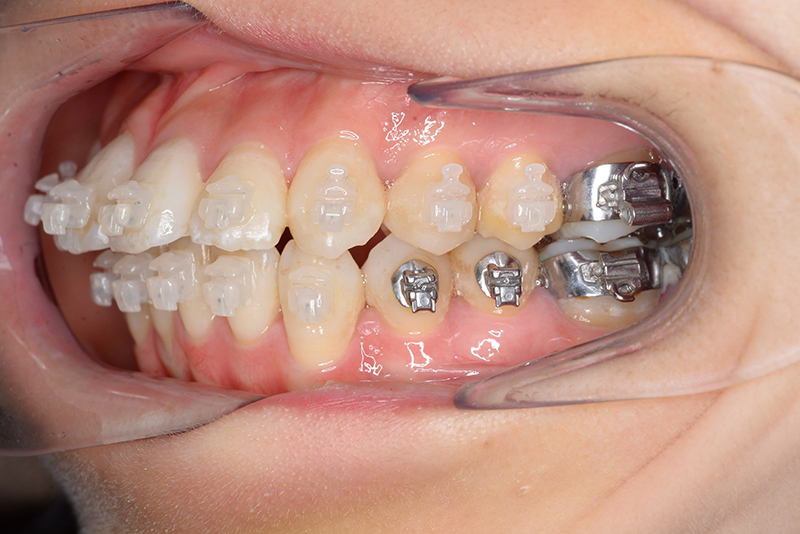

口腔内所見 over jet 4.0mm、over bite 2.0mm、臼歯関係Ⅰ級、犬歯関係Ⅱ級で上顎前歯は唇側傾斜を呈しており、上下顎前突の様相を呈していた。